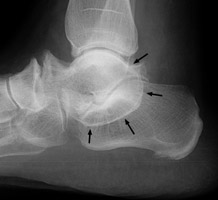

Lateral radiograph of the foot revealing a classic C sign which is a C-shaped line formed by the medial outline of the talar dome and the inferior outline of the sustentaculum tali. This is a sign of subtalar coalition. It is a reliable indicator of subtalar coalition on the lateral radiograph and represents the bony bridge between the talar dome and the sustentaculum tali.

Lateral foot - Click on the image for a larger versionACoronal CT - Click on the image for a larger versionB